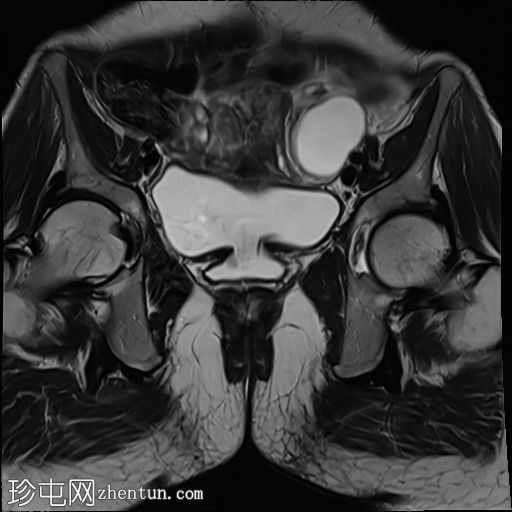

轴位

T2加权像

5.jpg

膀胱后壁与阴道前壁之间存在宽阔的瘘管。膀胱内可见气液平面。

阴道后穹窿上部与直肠中段前壁之间可见另一条较小的瘘管。在重扫描T2加权像上也可见。